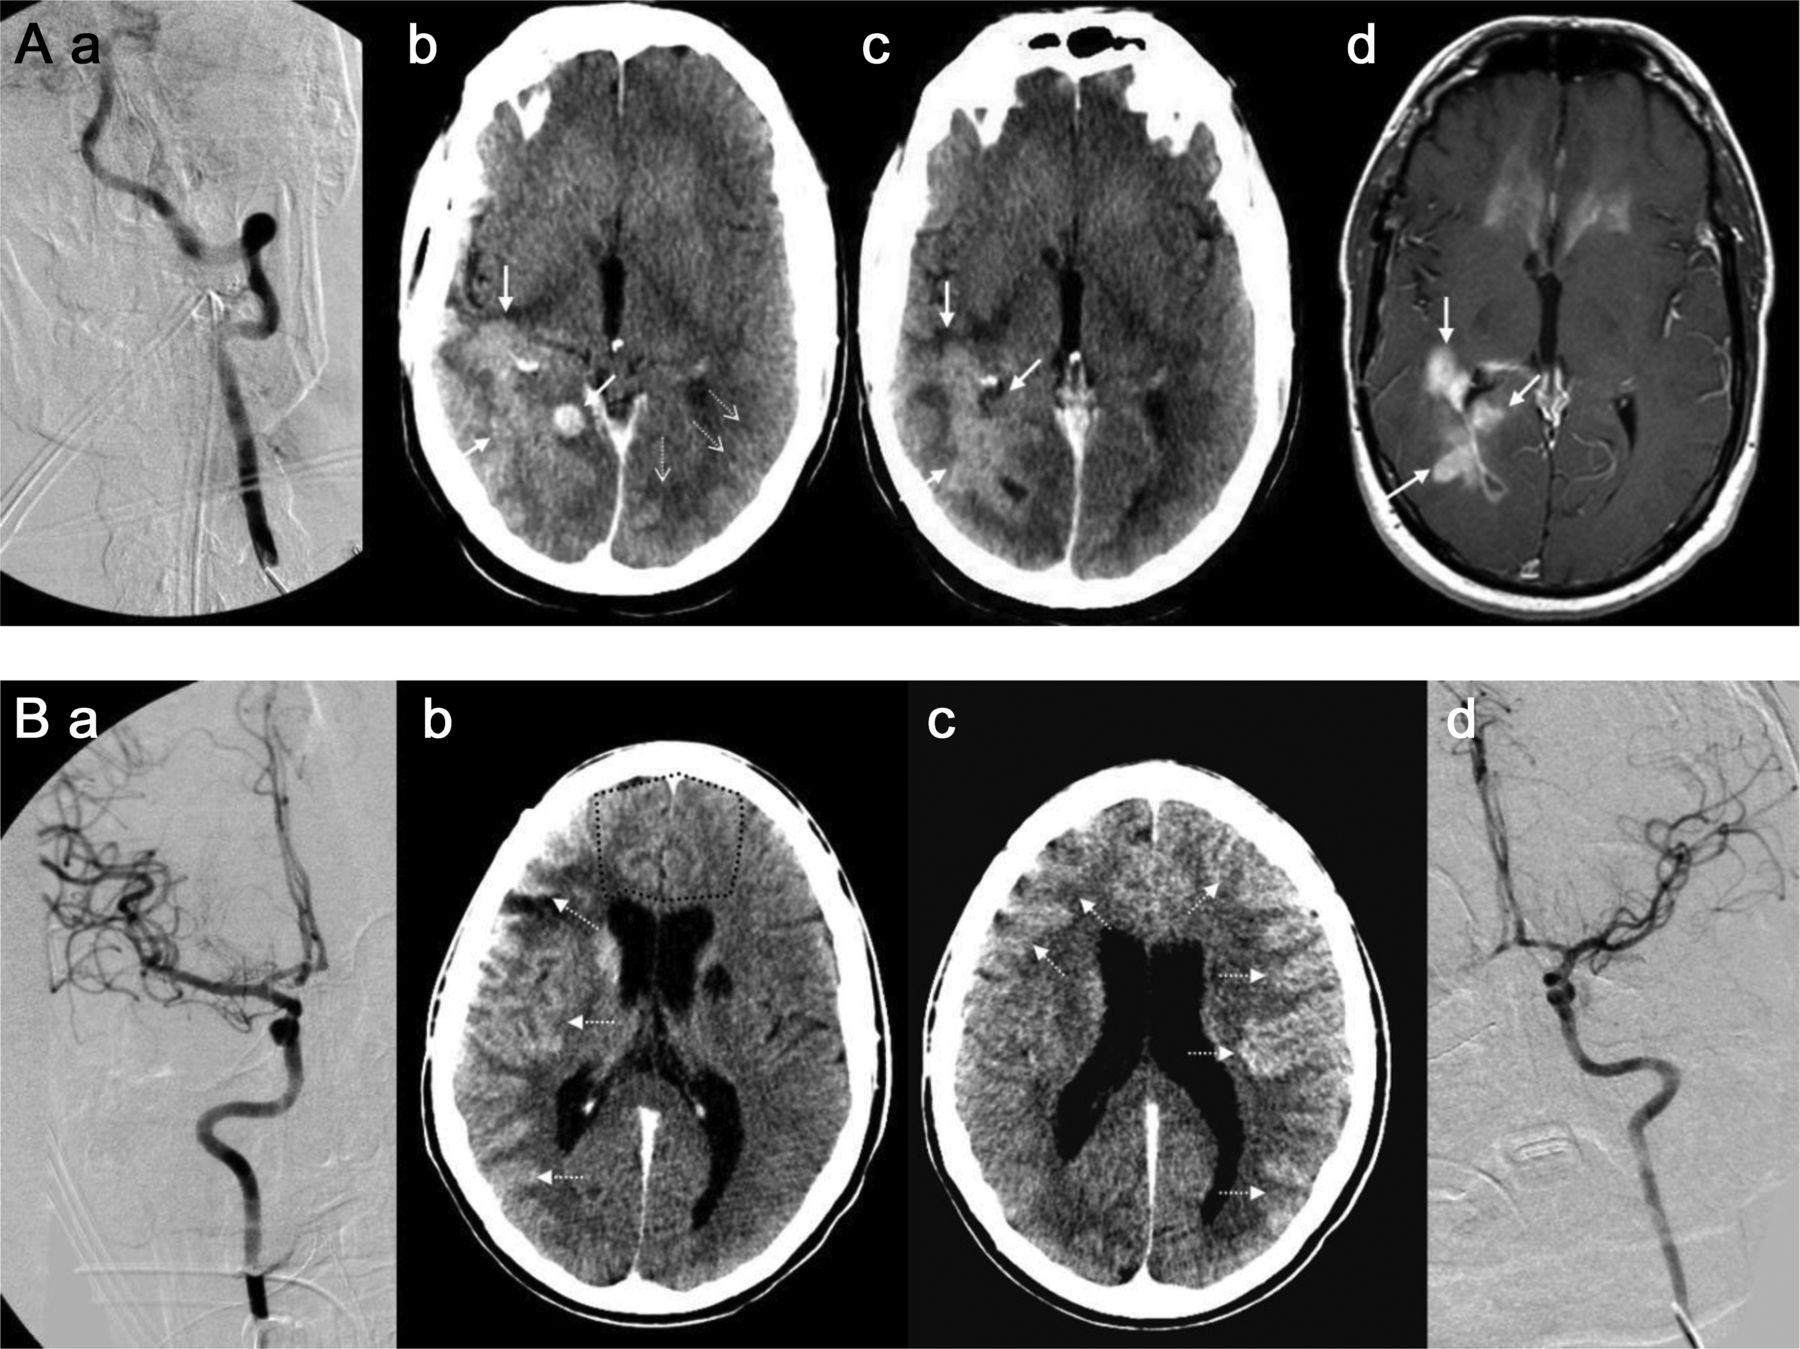

43岁的男人(A)与多形性胶质母细胞瘤(GBM)接受了血脑屏障的破坏(BBBD)通过左椎动脉导管造影(A)。在30分钟,对比增强CT表现,说明增强两国后大脑皮层的动脉(PCA)分布(虚线箭头表示正常皮质增强左侧)与增强肿瘤边缘围绕正确的侧脑室后角的(箭头,b, c),指出在postcontrast t1加权磁共振成像(d)。一个34岁的男人(b)与“绿带运动”接受了右颈内动脉(ICA)导管BBBD (A),与合成右大脑中动脉(MCA)分布增强(虚线箭头,b),备件ACA分布(虚线轮廓,c);缺乏cross-filling注意到A1段ACA,以及正确的MCA,通过前动脉和缺乏沟通PCA皮质分布增强(a)。第二天,病人接受导管BBBD通过ICA左边,与示范的双边ACA皮质分布增强(虚线箭头,c),这可能是由于为两国留住好的cross-filling以及A1段正确的ACA、MCA,看到通过ICA (d)。